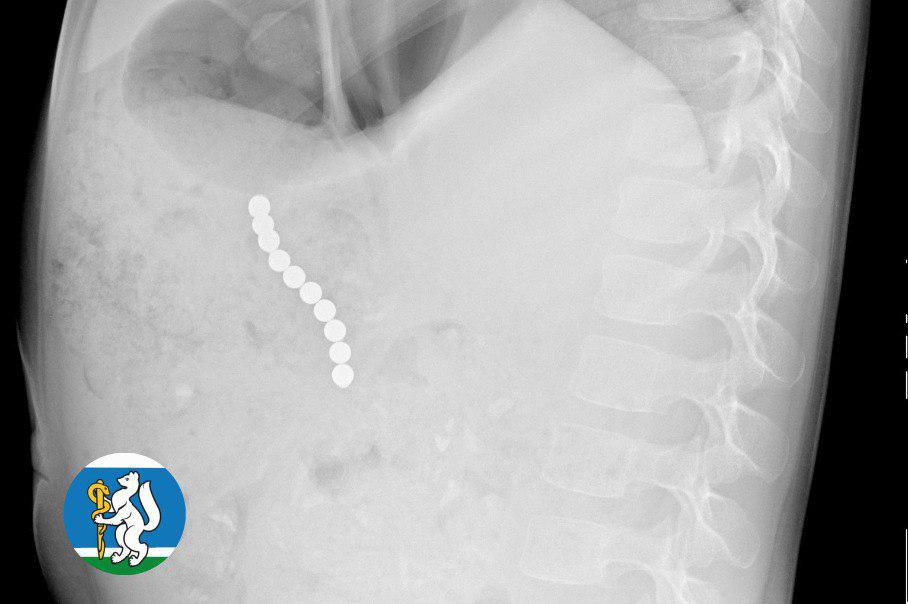

В Екатеринбурге хирурги спасли 5-летнюю девочку, которая проглотила 10 магнитных шариков. Инородные предметы выявил рентген грудной клетки, который сделали врачи для исключения пневмонии. После этого ребенка доставили в ДГКБ №9, где ему провели операцию.

«Для минимизации риска осложнений удаление инородных тел было проведено интраоперационно. В ходе вмешательства дежурная бригада врачей извлекла 10 магнитных шариков, цепочка которых в длину составила 5 сантиметров», — рассказал детский хирург ДГКБ №9 Андрей Чукреев.